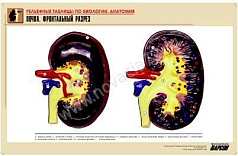

Комплект включает в себя 21 таблицу следующего содержания:

16. Почка. Фронтальный разрез;